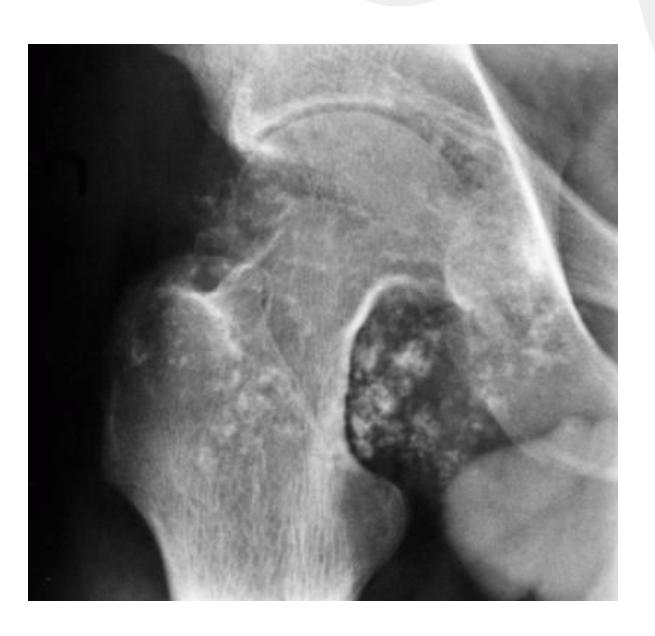

Brown Tumor

Clinical Features:

- Associated with hyperparathyroid disease

- Check PTH levels

- Differential diagnosis: infection, malignancy, hyperparathyroidism